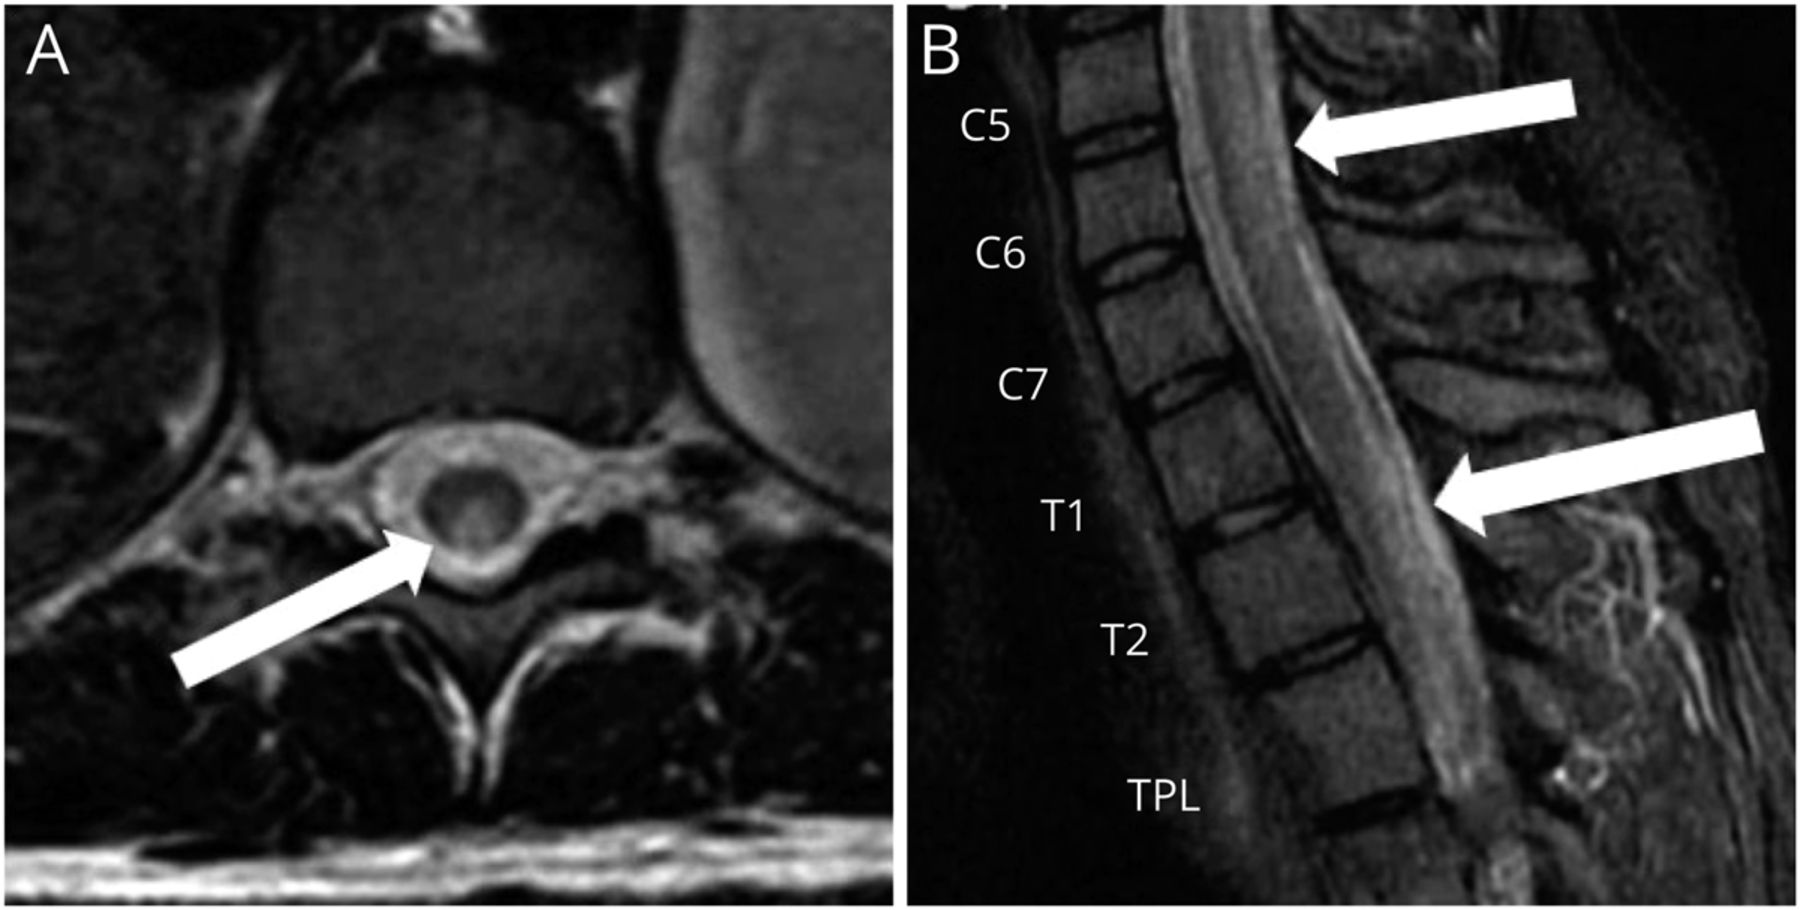

她最初看的是一位神经学家。当时的检查显示认知正常,颅神经完整,眼底正常,上肢力量正常。她的下肢弥漫性无力,全身力量为4/5。上肢反射正常,双侧髌骨有反射,双侧踝关节有阵挛。她的感觉检查显示双侧腿部振动感和本体感觉下降。温度和针刺感幸免。步态宽,需要助行器行走。颈椎和胸椎MRI显示从C5延伸至T11的脊背纵行广泛的T2高强度(图1).肌电图显示多处肌切面出现主动去神经。她的大脑核磁共振成像(图2)和实验室检查结果均不显著,包括正常的维生素B12 (625 pg/mL,参考范围232 - 1245 pg/mL),水通道蛋白4 (AQP4 Ab)阴性,髓鞘少突胶质细胞糖蛋白(抗MOG Ab)抗体阴性。此时未检测MMA和同型半胱氨酸。